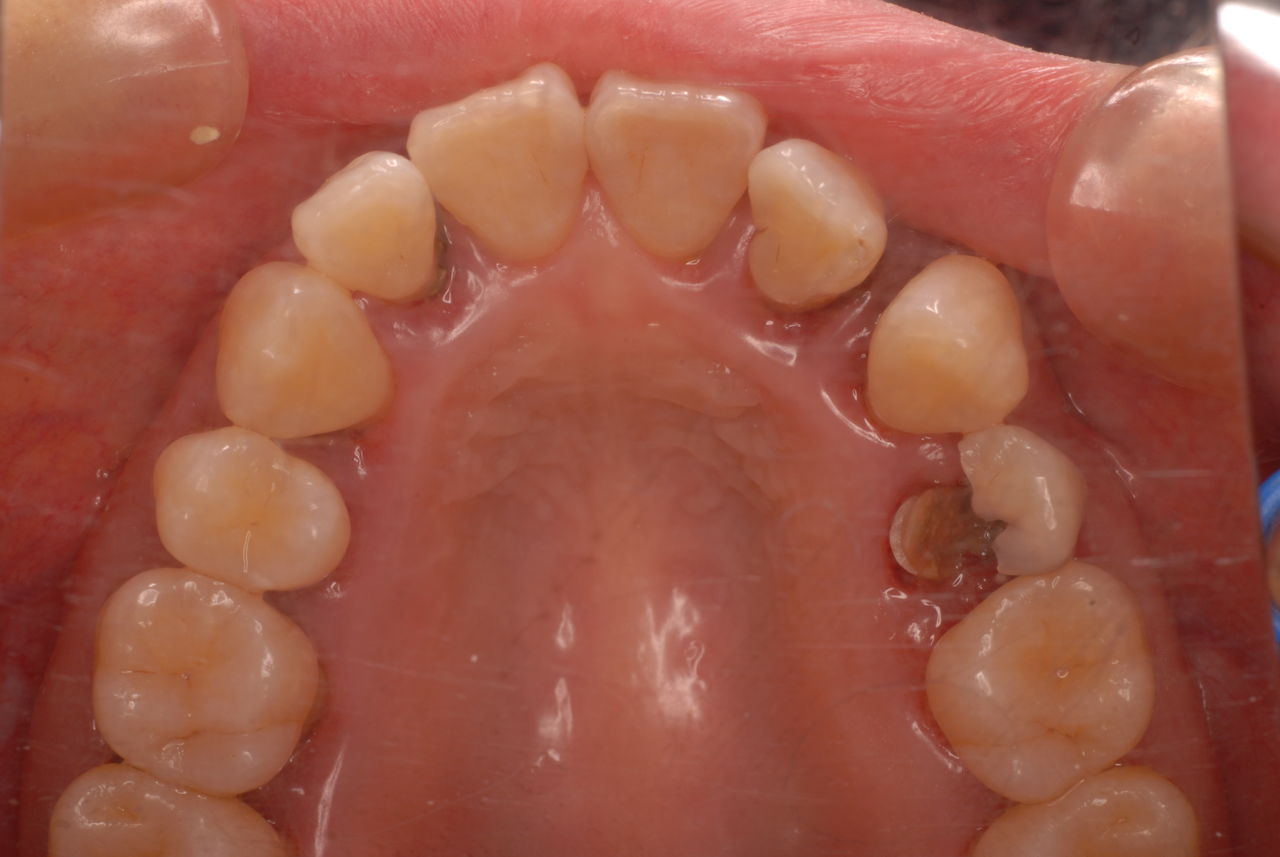

これができていない状態で何かを被せたり、詰めたりするから再発し加速度的に口の中は崩壊していくのです。

初診から数週間後大分よくなったとはいえまだまだ簡単な検査でも血だらけなのですね。